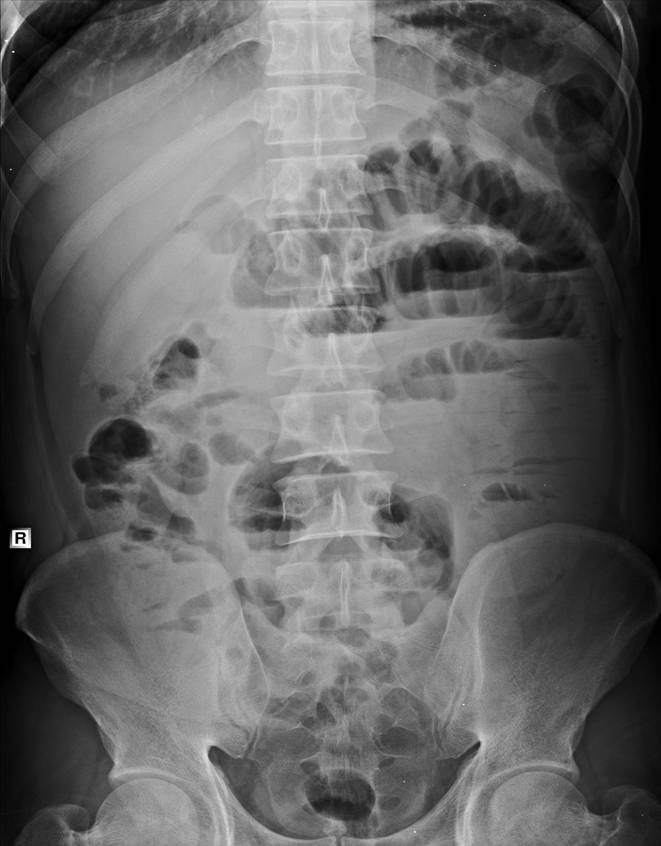

以下是引用zsl6918在2007-6-22 21:08:00的发言:[br]病史较长,反复发作,基本排除恶性病变,腹部定位像可见是小肠梗阻征象,原因无非是肠源性,血管性和神经性的,肠源性的在排除占位后应想到 肠旋转不良的可能,血管性的应想到肠系膜血管的栓塞,神经性的要想到植物神经功能紊乱的可能,本病例应该强化检查帮助诊断,个人感觉旋转不良可能性大。

以下是引用青莲居士在2007-6-24 12:27:00的发言:[br]肠梗阻[br]肝内胆管结石